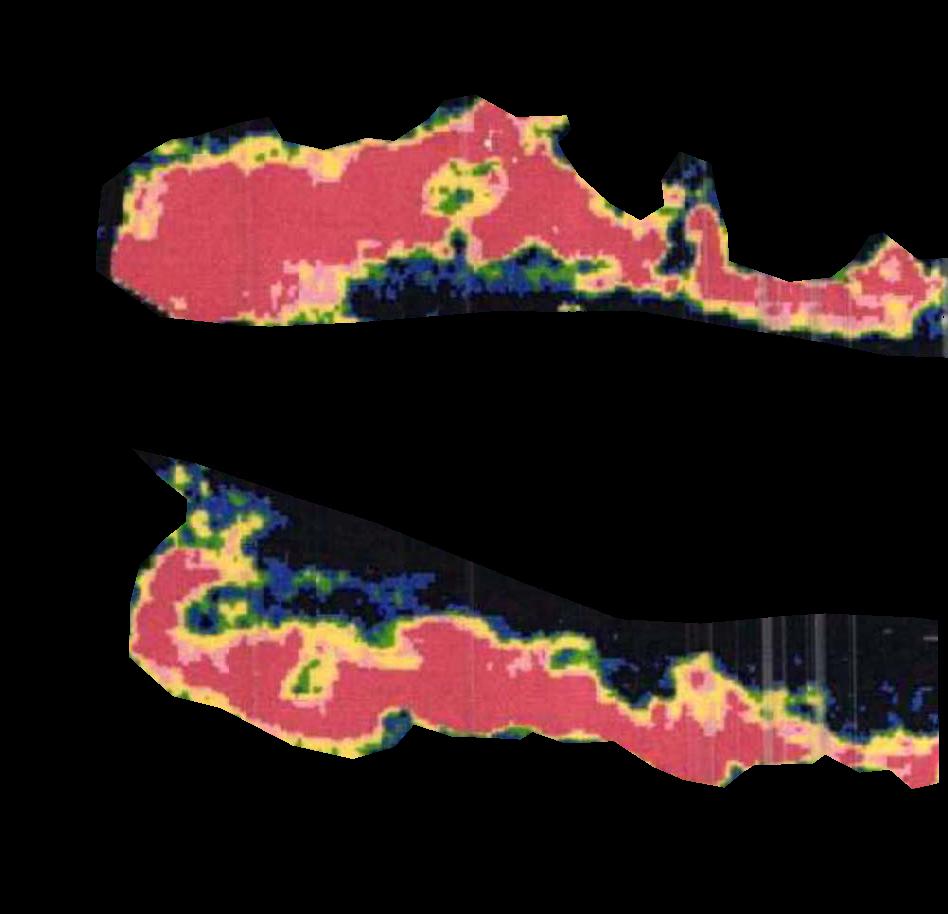

Figure 2a. illustrates the information retrieved from this CNN model from various layers of the architecture that is used to create a BAM map, which is used to segment the burn injury from normal skin in a 2D image. First, the heatmaps for the activations of the first convolutional layer are computed (Figure 2a(ii)), and then Grad-CAM heatmap is computed using the last convolutional layer (Figure 2a(iii)). Once the first convolutional layer heatmaps and Grad-CAM are generated, the algorithm uses a three-round iterative process to select activation heatmaps that have the highest correlation to the Grad-CAM heatmap among the channels of the first layer activations. After the process of correlating and selecting heatmaps is completed (Figure 3 ), segmentation masks are created next (Figure 4). A final composite BAM mask is created as illustrated in 2b(i). Finally, figure 2b (ii-iii) illustrates how the BAM mask is superimposed on the input image to segment the burn injury area, and how edge detection may be applied to the BAM mask in order to obtain a fine-tuned segmented boundary superimposed on the input image.

Figure 5 shows several burn image examples of patients with different sized burns in different body locations, for which the Grad-CAM heatmap, BAM heatmap, BAM masks, and final superimposed images were created. These results allow us to understand the clinical accuracy of burn segmentation from 2D images using BAM. These images show various degrees of burn. It is evident from the results that given skin burn images and the corresponding Grad-CAM heatmaps highlighting the burn regions even partially, the BAM heatmap is able to highlight the burn regions and display a high resolution heatmap accurately. This is the main contribution of BAM. It can be seen from the figure that the BAM heatmaps display different contrast levels in highlighting the burn regions. More precisely, the more superficial burns are highlighted with a lower contrast to the normal skin. The deeper burns, on the other hand, are highlighted with a higher contrast to the normal skin. Nevertheless, the contrast between the burn regions and the normal skin in the BAM heatmaps is sufficient for generating the binary segmentation masks even for the more superficial burns. As evidenced, the BAM heatmaps can successfully be converted into accurate binary segmentation masks. The rightmost column of the figure shows the BAM segmentation masks on top of the input images in order to better visualize the effectiveness of BAM in segmenting the burn regions. In short, comparing the Grad-CAM heatmaps against the BAM heatmaps and BAM segmentation masks provides evidence for a significant improvement in generating heatmaps that are both class-discriminative and fine-grained.

4 Quantitative Analysis

We evaluated the performance of the BAM in segmenting burn areas from images using a dataset of manual segmentations validated by clinicians of burn areas from 2D colour images. We also compared BAM against Laser Doppler Imaging (LDI) results, the gold standard for assessing the depth and healing potential of burns. LDI generates a map of the blood flow in different parts of skin (including the burn areas) using laser Doppler technology. During scanning, laser light enters the skin tissue and is scattered by moving blood cells in the tissue. As a result, the frequency of the light changes according to the Doppler effect; the higher the speed and concentration of moving blood cells in a tissue, the higher the amplitude of the laser Doppler signal. This blood flow image is used to calculate three categories of healing potential for burn wounds; 1) less than 14 days, 2) 14 to 21 days, and 3) more than 21 days Med (2021)Hoeksema et al. (2009). The colors of a blood flow image and their corresponding healing potential categories are illustrated in Figure 6.